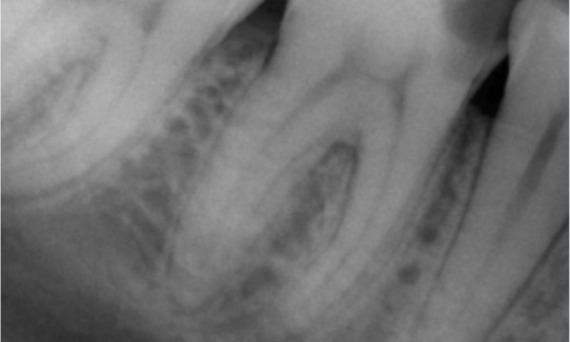

Antes: No exame, havia uma lesão de cárie dental relacionada ao primeiro molar inferior direito. O exame radiográfico revelou proximidade da lesão ao corno pulpar e, combinando-a com a queixa principal, concluiu-se um diagnóstico final de pulpite crônica irreversível.

Depois: A cavidade de acesso foi realizada da maneira mais conservadora possível. TruNatomy foi o sistema de escolha devido à idade do paciente jovem. Precisávamos preservar a dentina o máximo possível para aumentar a capacidade do dente de superar a carga oclusal e aumentar a longevidade da restauração final.

Dr. Ahmed Hussein Abuelezz (PhD em Endodontia)

Cairo, Egito